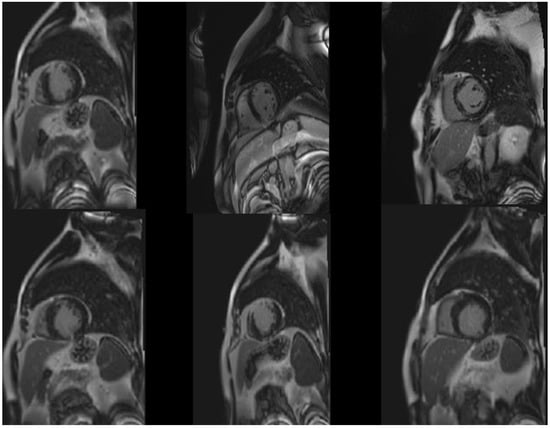

3.1. Dataset

3.2. Preprocessing